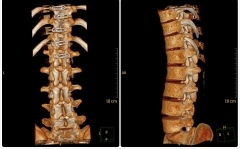

任性的脊柱神经外科手术可从“头”做到“尾”